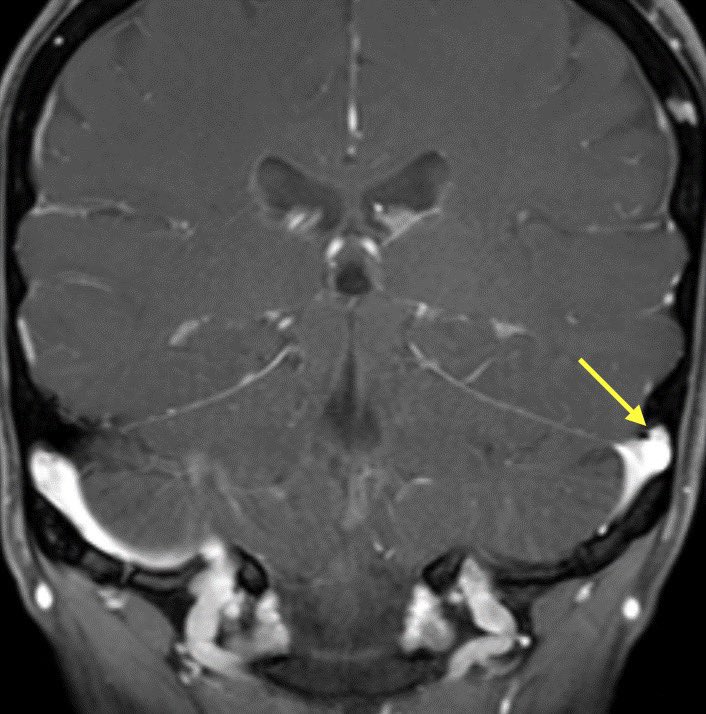

🔷TRANSVERSE SINUS STENOSIS & IDIOPATHIC INTRACRANIAL HYPERTENSION

EXTRINSIC: Defined as luminal narrowing with obtuse margins

🔹Typical cause of extrinsic stenosis is IIH though can occur without signs of IIH

💡Bilateral transverse sinus stenosis is seen in 94% of patients with lIH

💡 Stent placement is safe and effective in patients with transverse sinus stenosis (w/ or w/o lIH)